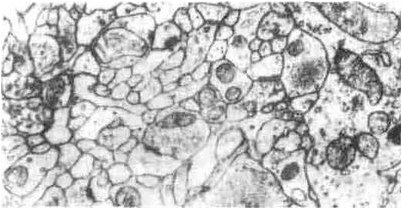

Для мозга для пребывания онлайновым этому нужна быстрая поставка кислорода и энергии. Теперь, нейробиологи идентифицировали клетки головного мозга, заказывающие кровоснабжение для жужжания частей мозга.

Понимание связи между мозговой деятельностью и изменениями в токе крови крайне важно для дальнейшего улучшения клинических сканирований головного мозга, таких как функциональная магнитно-резонансная томография (MRI), которые картируют изменения в мозговой деятельности через измерения тока крови. …